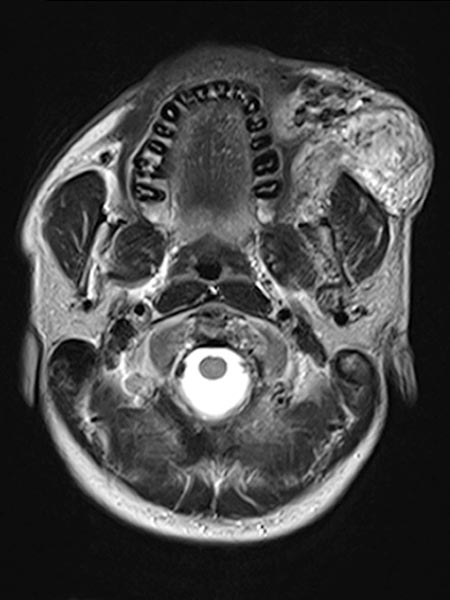

Axiale, T2-gewichtete MRT auf Höhe der Wange zeigt die AVM relativ hyperintens mit Ödem des Gewebes und Ausdehnung bis zum linken Unterkiefer. Im rostralen Abschnitt auch einige schwarze flow-voids durch stark durchblutete Arterien innerhalb der AVM.

Koronare, T2-gewichtete, fettgesättigte MRT mit Ödem innerhalb der AVM sowie gut sichtbaren flow-voids durch die enthaltenen Arterien mit hohem Durchfluss.

Inhomogenes, vor allem peripheres Enhancement der proliferierenden AVM in dieser axialen fettunterdrückten T1-gewichteten MRT nach Kontrastmittelgabe. Keine abgrenzbare, eigentlich solide Komponente, anders als bei einem echten vaskulären Tumor.